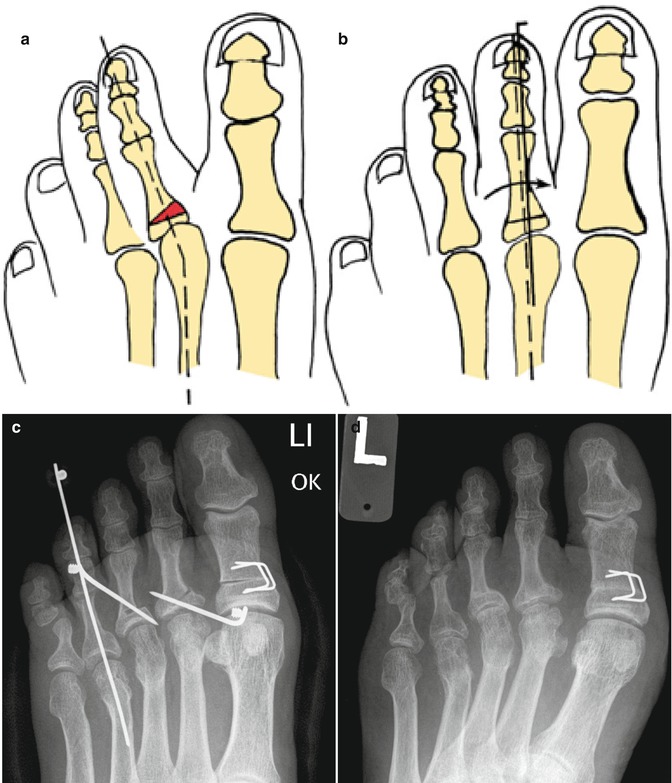

From www.foot.theclinics.com

Treatment of Flexible Lesser Toe Deformities Foot and Ankle Clinics Types Of Lesser Toe Deformities Sometimes they lose their straight shape and can become floppy or stiff. There are various types of lesser toe deformity and depending on the shape, we call these hammer, clawed or retracted toes. In the average person, there are three small bones (phalanges) in. The most common types of toe deformities are hammer toe, claw toe and mallet toe. They. Types Of Lesser Toe Deformities.